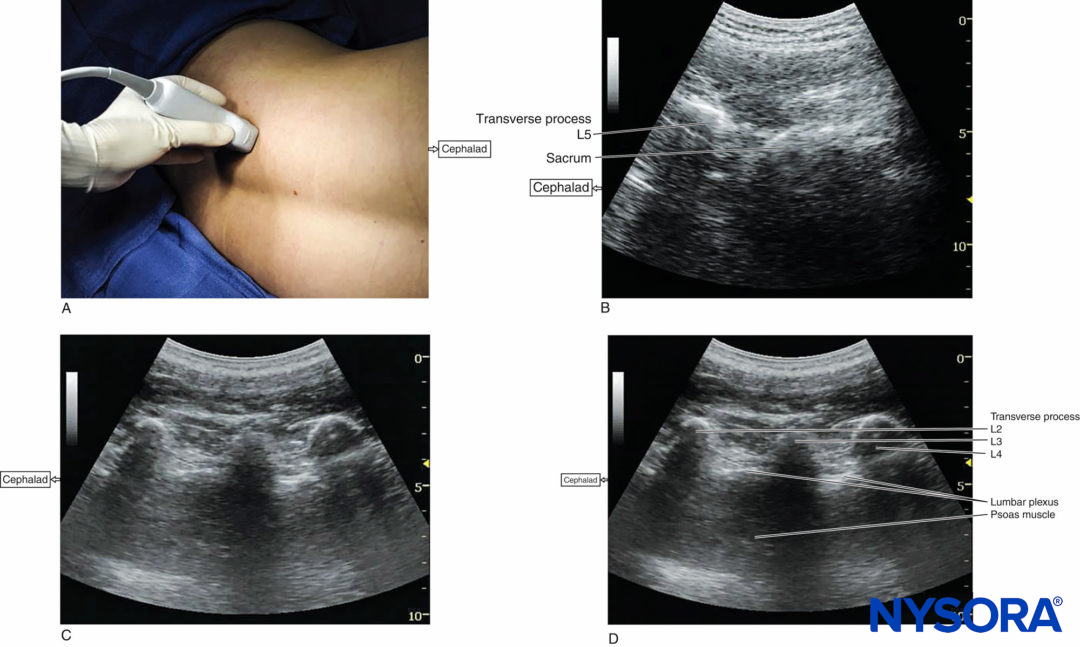

Regardless of technique, the patient is placed in the lateral decubitus position with the side to be blocked uppermost. The operator should identify the transverse processes on a longitudinal sonogram (Figure 1a, b, c). One technique involves identifying the flat surface of the sacrum and then scanning proximally until the intervertebral space between L5 and S1 is recognized as an interruption of the sacral line continuity (Figure 1b). Once the operator identifies the L5 transverse process, the transverse processes of the other lumbar vertebrae are easily identified by a dynamic cephalad scan in ascending order (Figure 1c, d).

FIGURE 1. (A) Transducer position to image the longitudinal lumbar paravertebral space including the transverse processes. Lumbar plexus block can be performed with this transducer position using both out-of-plane and in-plane approaches (see also Figure 4a). (B) Longitudinal US image of the lumbar paravertebral space demonstrating the sacrum and L5 transverse process. When the surface of the sacrum disappears, the next osseous structure is the L5 transverse process. (C) US anatomy of the lumbar paravertebral space demonstrating transverse processes at a depth of approximately 3 cm. The acoustic shadows of the transverse processes look like a trident. A lower-frequency, curved array transducer is used to optimize imaging at this deep location and obtain a greater angular view. (D) Labeled US image of Figure 1C.